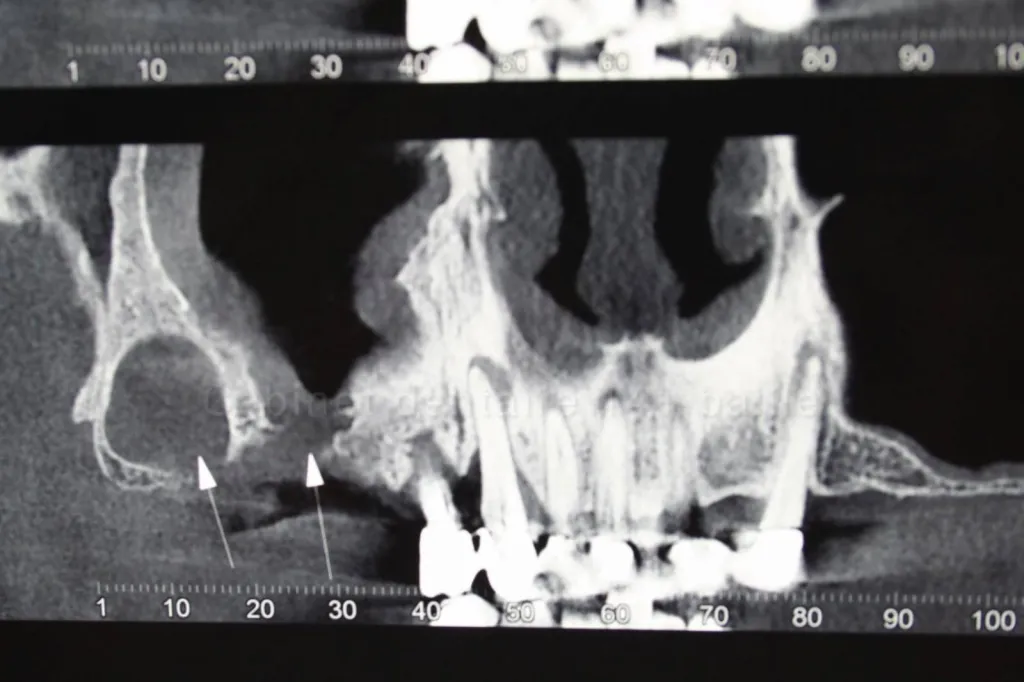

Dans ces cas il y a bien souvent trés peu de hauteur d'os dans les zones postérieures des arcades et  il est difficile d'implanter dans ces zones complexes sans avoir recours à des greffes osseuses dentaires  ou surélévations de sinus(sinus lift) qui alourdissent le traitement.

La technique Quattro ou encore appelée technique All on Four permet de reconstruire une arcade avec seulement 4 implants sur une arcade.